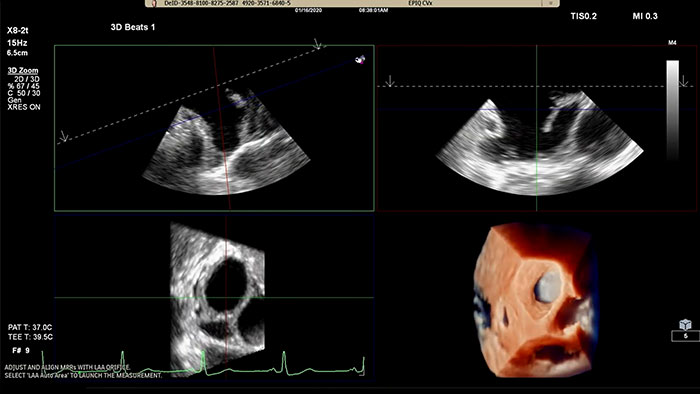

Assessing the left atrial appendage quickly, easily, intuitively.

The Philips LAA solution on EPIQ CVx.

Rapidly acquire LAA orifice measurements in both traditional rendering or in TrueVue Glass rendering, with 3D Auto LAA